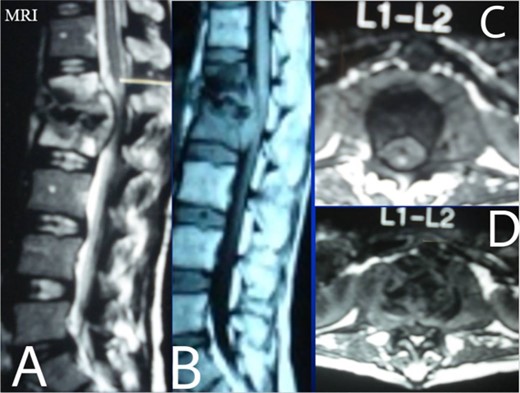

A 24-year-old farmer female was admitted to the Department of Neurosurgery with low back pain, no fever, cough, motor deficit, or any symptoms. Medical, surgical, family histories and physical examinations were unremarkable. The laboratory findings showed a white cell count of 9.8 × 103/μL, C-reactive protein concentrations of 20, erythrocyte sedimentation rate of 50 mm/1 h, 90 mm/2 h and tuberculin skin test was positive. X-ray films showed the collapse of the L1, L2 vertebrae, and L1–2 intervertebral space (Fig. 1). An abscess was observed at the L1–L2 vertebral level in lumbar magnetic resonance imaging (MRI) (Fig. 2). Chest X-rays and Sputum smear were negative. The patient was treated with anti-TB treatment (Isoniazid, Rifampicin, Ethambutol, Pyrazinamide) due to spinal TB findings on MRI (Fig. 3). After 40 days, the patient was diagnosed with grade 1/5 lower limb weakness, and bladder and bowel dysfunction, with no impairment in sensation, which predicts spinal infection. MRI confirmed these abnormalities and showed typical findings such as vertebral endplate destruction, bone marrow and disk signal abnormalities, and paravertebral or epidural abscesses (Fig. 3). Due to clinical manifestations and MRI spinal TB findings (Fig. 3), the patient underwent surgical debridement, interbody fusion and internal fixation with fibular autografting and supplemental posterior spinal stabilisation using a posterior-only approach. On post-operative follow-up, the treatment continued for 9 months, in addition to physical therapy for lower limb weakness. In the end, the patient returned to full motion with grade 5/5 in the lower limb, normal sensation, and no bladder or bowel incontinence. No recurrence was observed in the grafting area. Radiologically 2, 6 and 12 months, 14 years’ post-operation, the patient had achieved full bony graft spinal fusion (Figs 4–6).

Sagittal T2-weighted MRI shows severe disco vertebral destruction, the formation of epidural abscess and compression of the spinal cord at the L1–2 level.

Lumbar T1 and T2 consistent with an abscess at the L1–2 vertebral level. (A) and (B) showed that the height of the L1 and L2 vertebral bodies was markedly reduced and the dural sac and spinal cord were severely compressed by an abscess posterior to the vertebral body. (C and D) Axial T1 shows a well-defined paraspinal abscess. The anterior epidural abscess compresses the spinal cord.